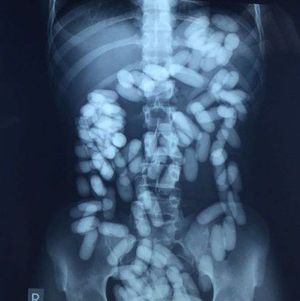

Well well, We have kind of seen something similar to what this X-Ray shows, but some are fake! This is my friends one case reported from the airport of 20 year old guy smuggling drugs in capsules by keeping them in his gastrointestinal tract!, but for sure he got caught and was transferred to the section I was in. It was an interesting case to see and thought you wouldn't wanna miss it too!